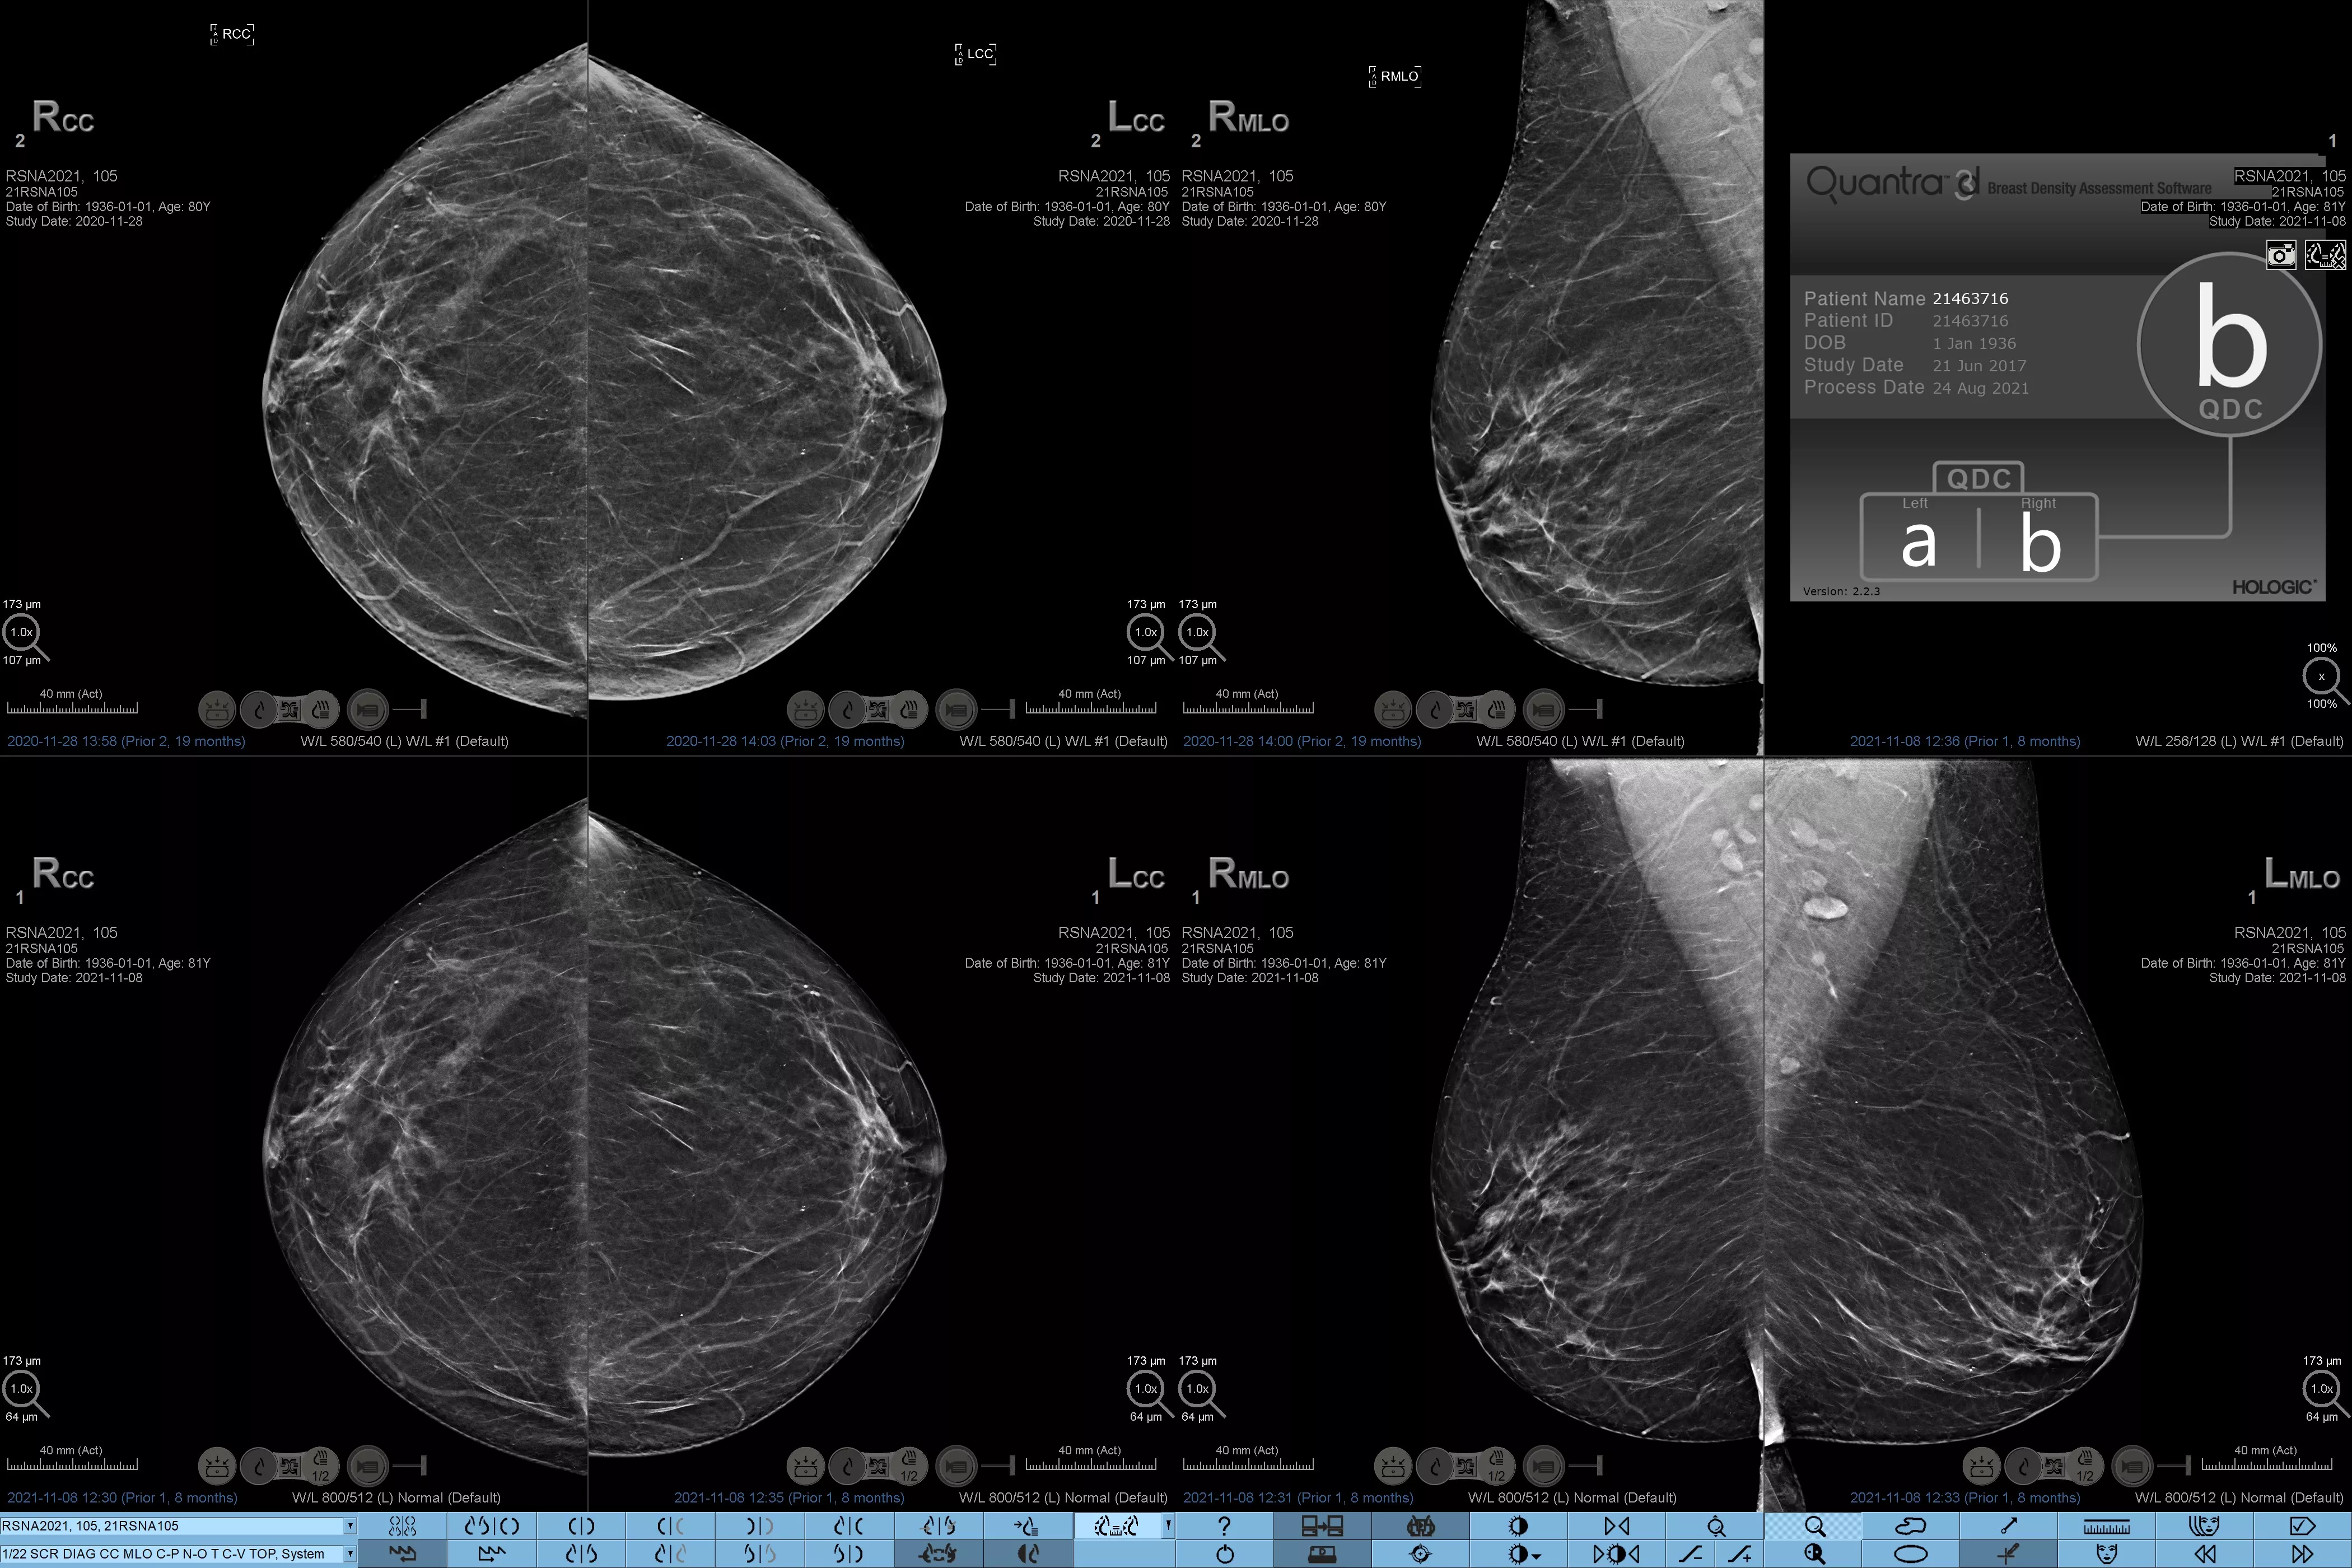

Higher breast density is known to increase a woman’s risk for breast cancer.1 The need for accurate, unbiased analysis is therefore critical. Powered by machine learning, Quantra technology software analyses both 2D™ and tomosynthesis images for distribution and texture of parenchymal tissue. It categorises breasts in four breast composition categories consistent with guidance from the American College of Radiology (ACR) BI-RADS Atlas 5th Edition.2

In addition to volume, pattern and texture of fibroglandular tissue may play just as an important role in mammographic cancer risk prediction.3-5 By analysing and categorising breast texture and pattern, our technology can deliver the accurate information you need to achieve more consistent and reliable scoring and confidently design patient-specific screening.

Objective machine learning algorithm that assigns breast density category based on analysis of breast tissue texture and patterns.

Quantra software’s unbiased algorithm analyse both 2D and tomosynthesis images to support your analysis by:

• Overcoming subjectivity in visual assessment, providing more consistent, and more reliable scoring.*

• Elevating the standard of care and standardises reporting.

*Scores are based on ACR BI-RADS categories, in line with the revised guidance by the American College of Radiation (ACR) BI-RADS Atlas 5th Edition. This accounts for pattern and texture, compared with volume, when determining density.